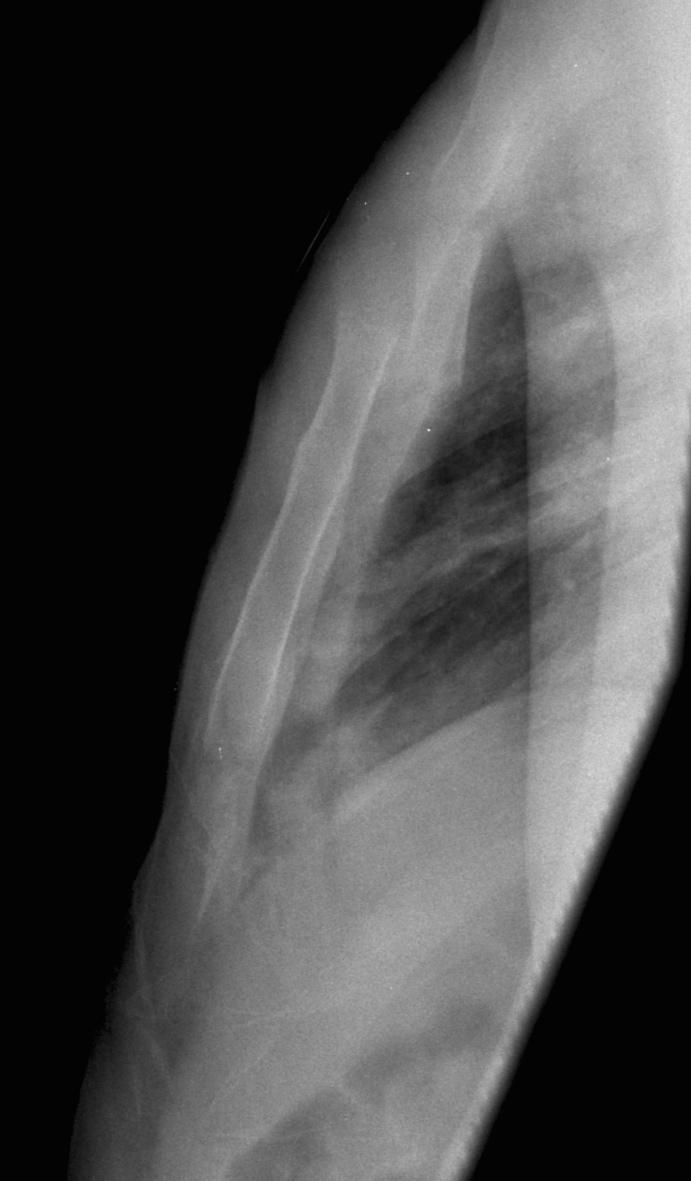

Rib Fractures Supine Haemothorax